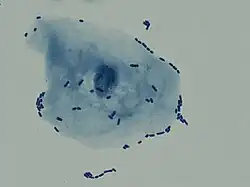

Multiple bacilli (rod-shaped bacteria, here shown as black and bean-shaped) shown between white blood cells in urinary microscopy. These changes are indicative of a urinary tract infection.

In straightforward cases, a diagnosis may be made and treatment given based on symptoms alone without further laboratory confirmation.[4] In complicated or questionable cases, it may be useful to confirm the diagnosis via urinalysis, looking for the presence of urinary nitrites, white blood cells (leukocytes), or leukocyte esterase.[54] Another test, urine microscopy, looks for the presence of red blood cells, white blood cells, or bacteria. Urine culture is deemed positive if it shows a bacterial colony count of greater than or equal to 103 colony-forming units per mL of a typical urinary tract organism. Antibiotic sensitivity can also be tested with these cultures, making them useful in the selection of antibiotic treatment. However, women with negative cultures may still improve with antibiotic treatment.[4] As symptoms can be vague and without reliable tests for urinary tract infections, diagnosis can be difficult in the elderly.[11]